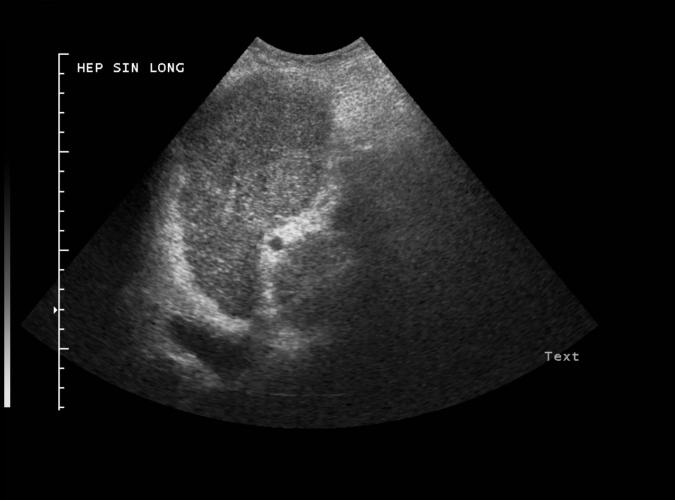

Diskret fokal förändring ventralt i vänster leverlob hos en

patient med levercirrhos. Vidare utredning visade hepatocellulär cancer...se trans. bild 2i